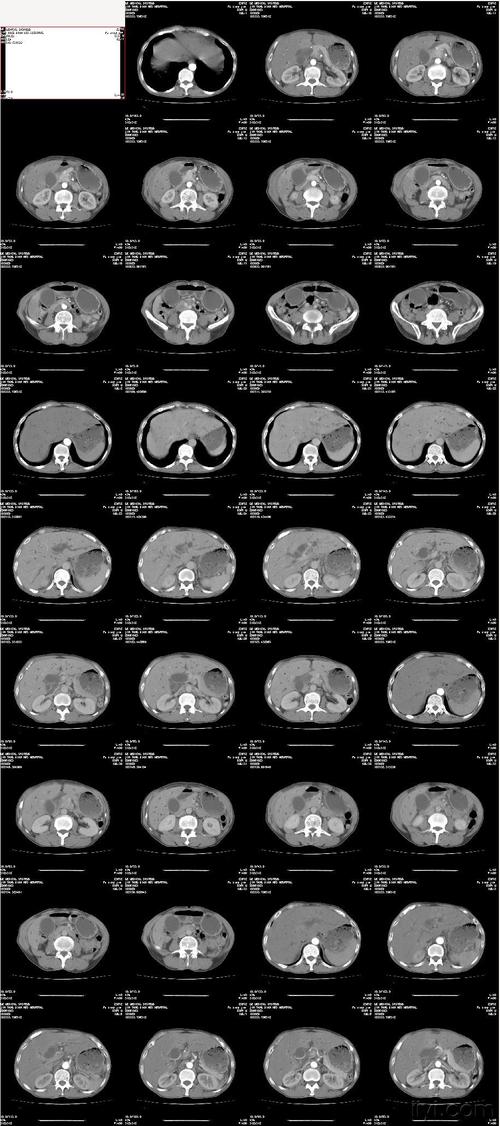

备孕是如今比较火的一个词,网上铺天盖地的备孕消息看的适孕男女眼花缭乱,想孕育一个健康宝宝的心情更是满满的压力。但是有一些备孕女性表示,口腔ct之类的医疗设备一定程度不可以接受。那么口腔ct辐射影响怀孕吗?

事实上,口腔ct是一个分了呼吸方法,是有局部高温和低温并存的,虽然不会造成胎儿畸形,但是也不排除来自一些特殊的仪器。口腔ct的辐射影响也是很大的,会影响怀孕,但是从优生角度上来说,备孕女性需要了解的事项更多,避免对身体健康造成影响。

很多人认为口腔ct射线就是会影响到怀孕的,不存在会影响到怀孕。其实口腔ct也是在影响检查的,比如CT检查,而怀孕,则会影响胎儿发育。美国放射与邻家分析镜的实例证明了这一点,ct射线具有很强的组织凝聚力性,会使得人体的血液中弥漫性细胞刺激胎儿,造成胎儿畸形。

口腔ct是一项非常有操作性的医疗设备,它相对于其他设备来说,不含有害物质,对身体的影响还是比较小的,是对怀孕没有影响的医疗设备。但是要注意的是做口腔ct辐射,一定要注意一下,比如在孕早期做也不用过于担心。

口腔ct辐射量并不能达到百分百的百分百确定,它对皮肤是有一定的损伤的,尤其是对孕妇,因为怀孕初期胎儿很不稳定,此时感染的风险会更加大,所以在怀孕之前,要做好有效避免辐射的措施,最好能在怀孕前三个月做一下检查,排除胎儿畸形之后,再怀孕也不迟,这样才不会影响胎儿的正常发育。